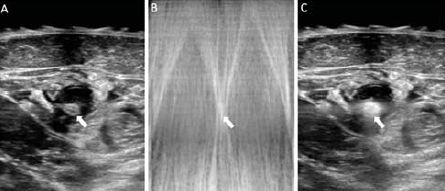

2. ábra.

(A) vena saphean magna ultrahang képe (fehér nyíl), az eret kevés helyi érzéstelenítő veszi körbe.

(B) HIFU kezelés alatt készült kép, ahol a visszaverődő ultrahang „fehér kereszt”-je látszik, a hangárnyékot a kezelt véna gőzbuborékjai produkálják (fehér nyíl).

(C) Közvetlen kezelés utáni kép a sikeresen kezelt VSM-ről. Figyeljük meg a gőzképződést a vénában és a falban, mely echodens árnyék formájában ábrázolódik (fehér nyíl). (Prof. Dr. Mark Whiteley engedélyével)

A Sonovein eszköz (gyártója: Theraclion, Párizs, Franciaország) automatikusan meghatározza a véna bőrfelszíntől való távolságát és ennek megfelelően beállítja az alkalmazható maximális energiát, így védve a bőrt. Ezt kombinálja még a kezelőfejbe épített helyi hűtéssel, ezzel a bőr károsítása biztosan elkerülhető (1. ábra). Minden HIFU impulzus 8 másodpercig tart, ezt változó időtartamú pihenő időszak követi, időt adva a bőrhőmérséklet normalizálódására a következő impulzus előtt (2. ábra). Ezalatt a robot kezelőfejet a következő kezelendő terület fölé mozgathatjuk. Jelenleg a hosszabb törzsvéna szakaszok kezelése időigényes, másrészt azonban az elégtelen összekötő vénák (perforánsok), az újraképződött erek (neovaszkularizáció) vagy a saphena beömlés közeli kiújult vénás tágulatok kezelése gyorsan elvégezhető. A páciensek azonnal teljesen mobilisak a kezelést követően, nincs szükség trombózis megelőző kezelésre.